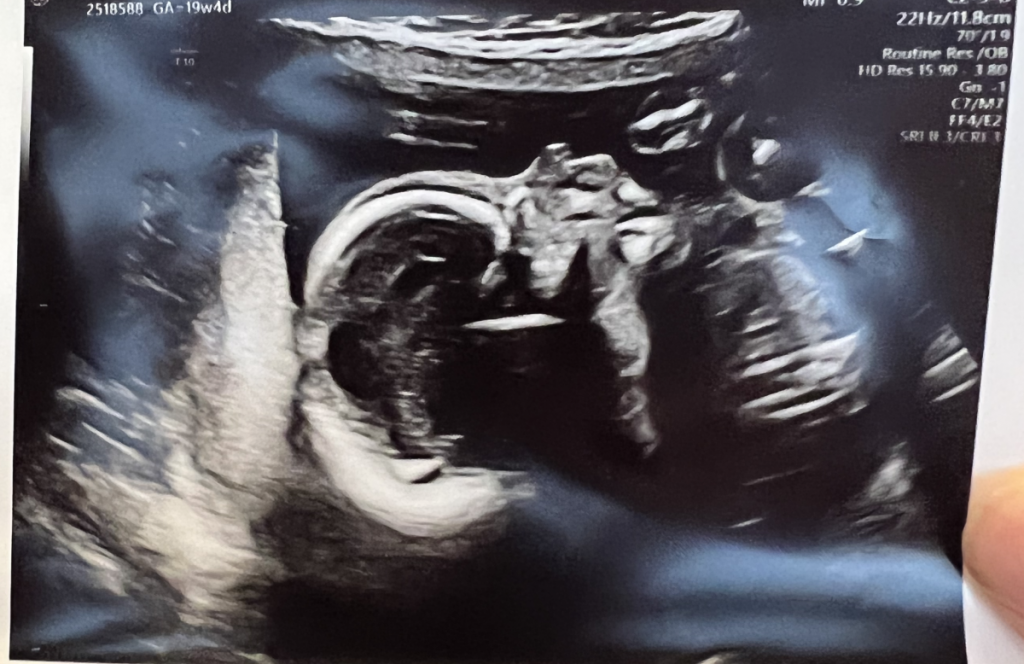

Está claro que este blog será o el caos o la nada. Si sigo buscándole un orden, me veo dentro de un par de años volviendo a contar en Twitter que quiero escribir más, así que antes que eso prefiero abrazar el caos y escribir de lo que toque en cada momento. También es verdad que lo que toca hoy no es que toque, es que posiblemente venga a llenarme la vida de caos. Aquí lo tenéis. Esta semana hemos estado en la ecografía de las 20 semanas.

A propósito de esto un par de cosas que me merece la pena anotar. Primero, pensar que se está formando una persona dentro de otra se me hace entre mágico y alucinante. Alucina que ocurra y la velocidad a la que lo hace. La madre de Charlotte nos decía hace unas semanas en Vancouver que era eso mismo lo que le dejaba sin palabras: «Nueve meses, y de aquí (señalándose a la barriga) ha salido otra persona». Nueve meses para que salga pero en la primera ecografía, a las 12 semanas, ya estaba prácticamente todo ahí. Un montón de células que empiezan a dividirse y a especializarse y en un puñado de semanas ya se están organizando en el tamaño de la palma de mi mano pero con todo ahí: cara, cráneo, un cerebro con sus dos hemisferios, un corazón que lleva semanas latiendo, brazos, piernas, su columna vertebral y hasta una actitud de «déjame en paz» cuando el médico intenta hacerle cambiar de posición con la sonda del ecógrafo.